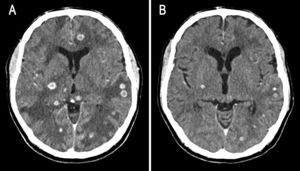

Se presenta el caso de un hombre de 64 años que consultó por malestar general, pérdida del equilibrio y anorexia. No explicaba cefalea, fiebre u otros síntomas. No tenía antecedentes médicos ni hábitos tóxicos destacables. En la exploración física destacó dismetría y marcha lenta e inestable. El examen de fondo de ojo fue normal. Analíticamente presentaba proteína C reactiva elevada (59,63 mg/l) sin leucocitosis. La radiografía de tórax y el electrocardiograma no mostraron hallazgos. La tomografía computarizada craneal reveló múltiples lesiones nodulares con realce difuso en anillo, de distribución en el cerebelo y el parénquima cerebral, con edema perilesional (fig. 1). Se inició dexametasona y el estudio en medicina interna. Los marcadores tumorales y las serologías realizadas (VIH, VHC, VHB, Treponema pallidum, citomegalovirus y toxoplasma) fueron negativos. La tomografía computarizada toracoabdominal mostró 2 tumoraciones parahiliares izquierdas sospechosas (fig. 2A) y adenomegalias mediastínicas y axilares (fig. 2B). La broncoscopia fue normal y no se encontraron células malignas en el lavado broncoalveolar. La biopsia de un ganglio axilar izquierdo evidenció granulomas epitelioides con células gigantes multinucleadas tipo Langerhans y necrosis caseificante central. Se inició el tratamiento empírico con isoniazida, rifampicina, etambutol y pirazinamida. Posteriormente, se aisló Mycobacterium tuberculosis en el cultivo del lavado broncoalveolar, no así en el líquido cefalorraquídeo. El ensayo de liberación de interferón gamma (IGRA) fue positivo y los hemocultivos fueron negativos. A las 3 semanas del tratamiento se observó la mejoría radiológica (fig. 3). El paciente completó 9 meses de tratamiento y alcanzó la curación.